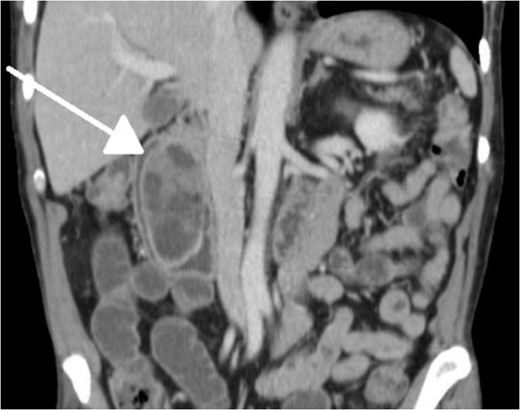

Small bowel series showing duodenal filling defect (posterior view).

Small bowel series showing duodenal filling defect (anterior view).

With regard to diagnostic workup, the literature has described cases with similar results to ours. Small bowel contrast studies frequently show smooth-walled polypoid filling defects within the duodenal bulb, and CT imaging is useful for delineation of adjacent structures including the common duct and pancreas [1]. Moreover, similar to the pathological results found in our patient, upper endoscopy biopsies are often equivocal as they are submucosal-based lesions [1]. The most useful diagnostic study, however, is endoscopic ultrasound, which may help distinguish the consistency and bowel layer of origin [2, 6], which unfortunately was not available at our institution.